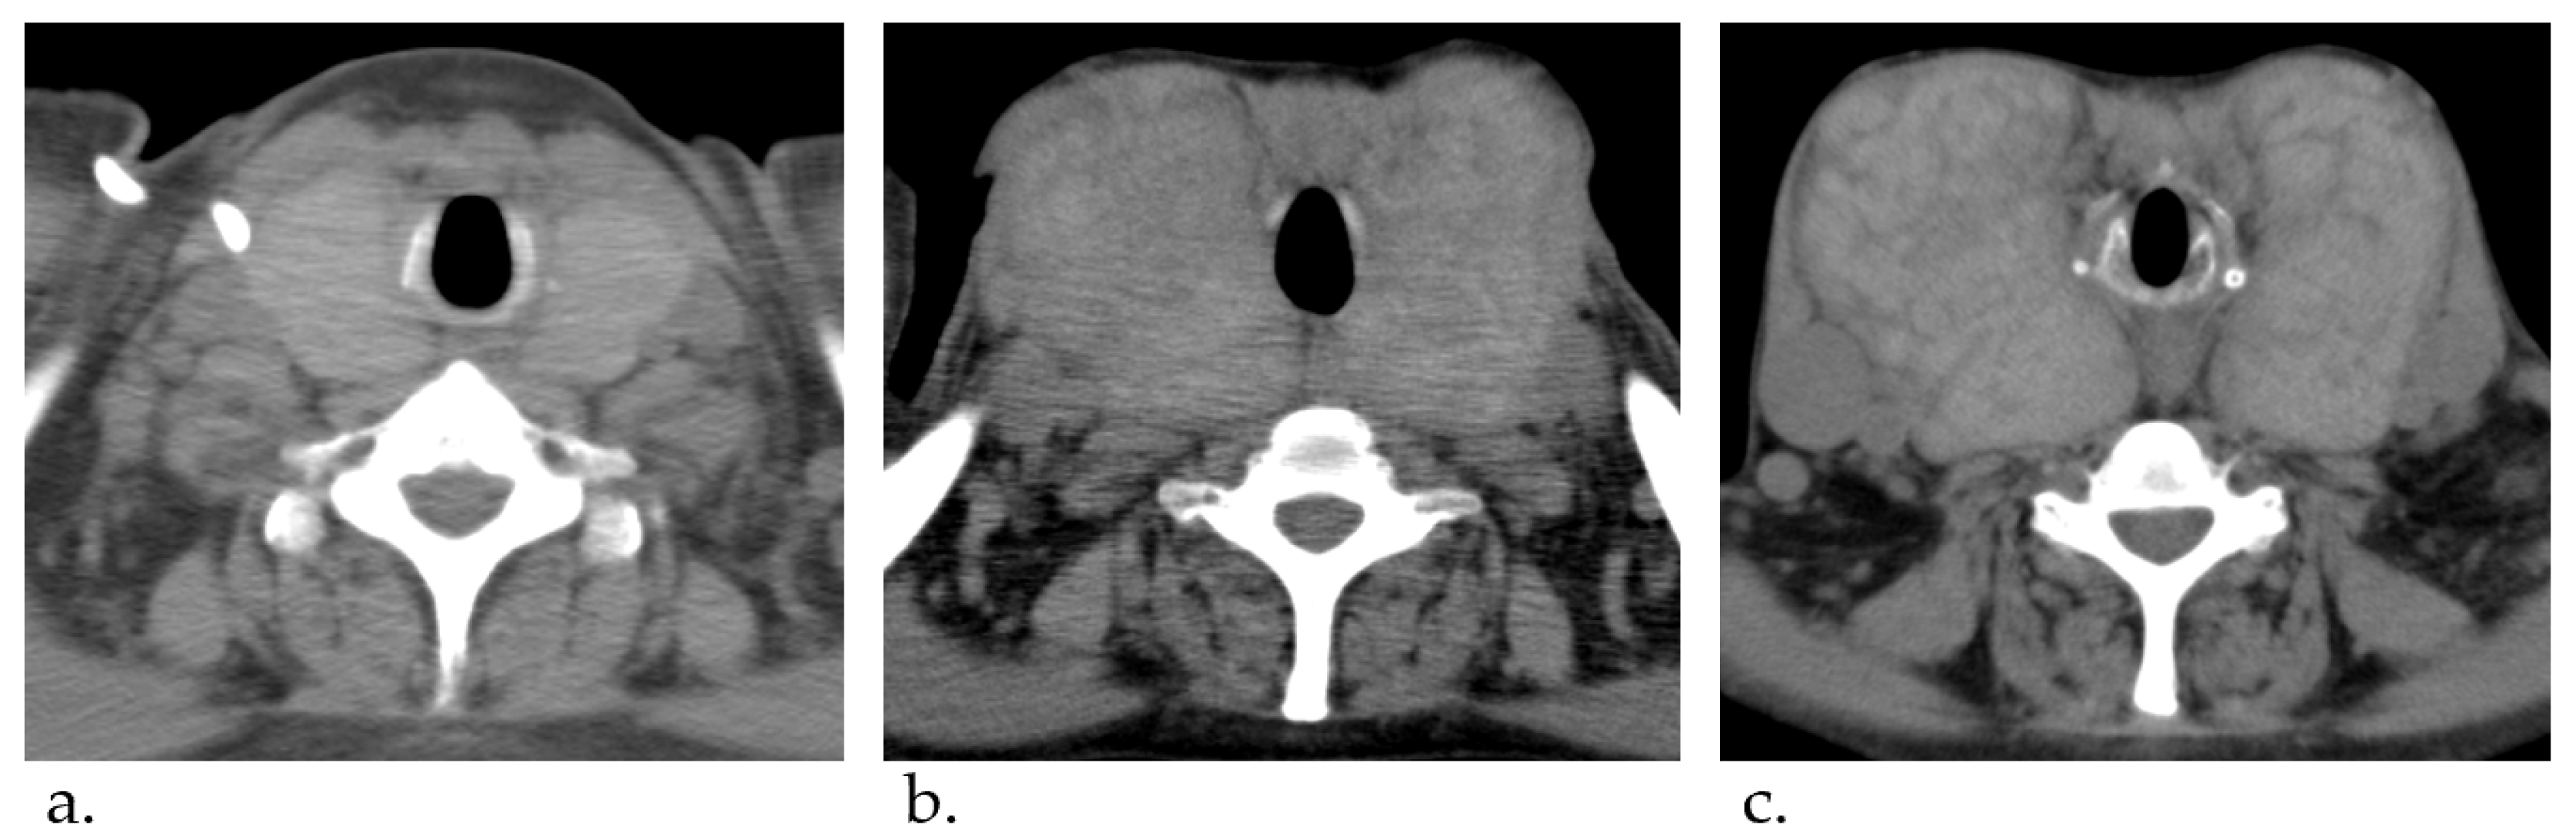

A Case of Giant Goiter Associated with Airway Stenosis Caused by Long-Term Intravenous Epoprostenol Therapy for Idiopathic Pulmonary Arterial Hypertension

2. Case Report